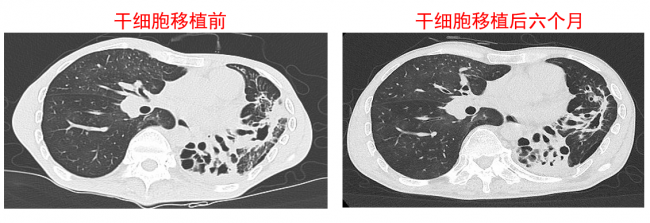

在东方医院的呼吸科室,已有数位肺病患者接受了自体肺脏干细胞的移植。从这些患者支气管刷取出的几十个干细胞,在体外扩增数千万倍之后,被移植到他们肺部的病灶部位。经过3至6个月的增殖、迁移和分化,干细胞逐渐形成了新的肺泡和支气管结构,成功实现了对患者肺部损伤组织的修复替代。患者的肺换气能力DLCO、六分钟步行距离等指标得到不同程度的改善。在肺部CT影像上,也可清晰观察到干细胞对肺部病变组织的修复替代。

在该研究论文中描述的,是最早接受自体肺干细胞移植的两例支气管扩张患者,两人接受移植距论文发表已有超过一年半的时间。移植一年之后,两位患者均自述咳嗽、咳痰和气喘等症状出现改善。CT影像学显示,其中一位患者的支气管扩张结构一年后呈现局部修复状况,肺功能检测提示移植干细胞一个月后肺功能尚未好转,而等到三个月之后各项肺功能开始出现好转,效果一直保持到一年之后。